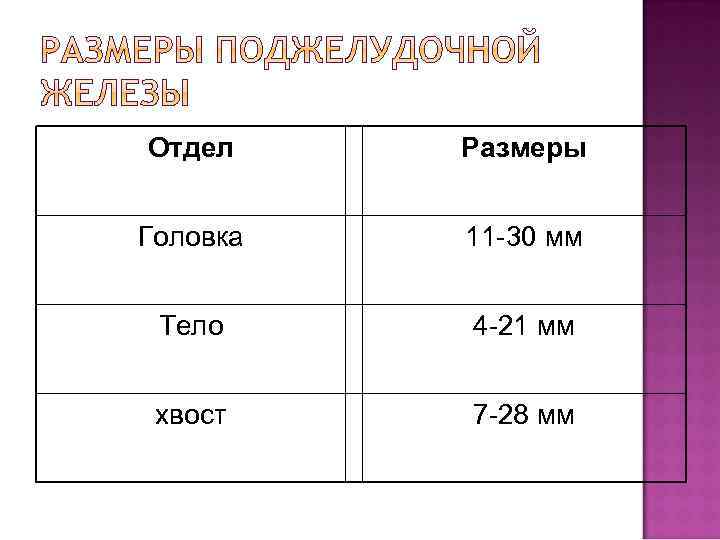

Отдел Размеры Головка 11 -30 мм Тело 4 -21 мм хвост 7 -28 мм